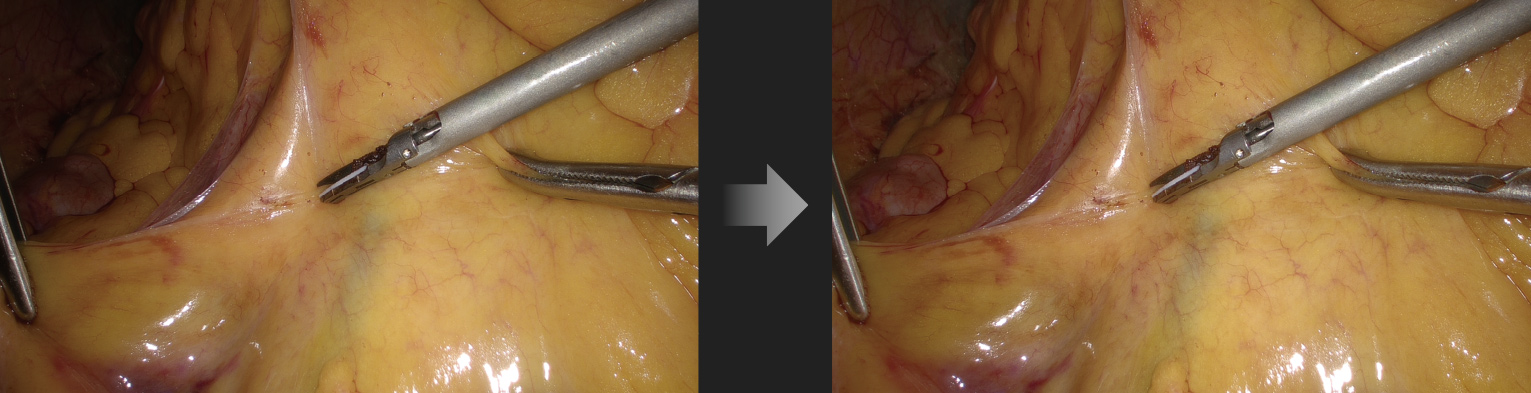

Automatic Scene Recognition, Intelligent Brightness Adjustment

Smart exposure: Determine different detection areas according to different scene and accurately match the exposure parameters without the need to manually switch department modes.

Small diameter scope scene (e.g. hysteroscope)

Laparoscope scene

Automatic dimming: The camera system can automatically adjust the intensity of the light source in real time according to the exposure requirements of the current image, and ensure appropriate brightness.